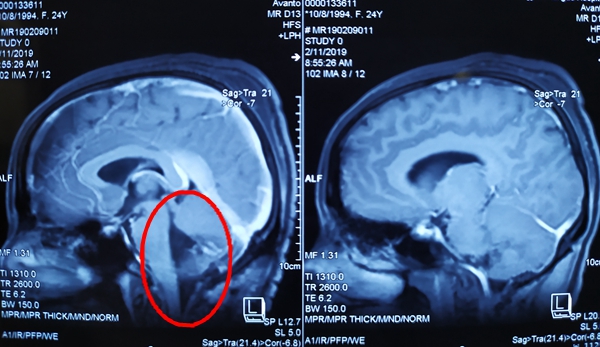

到达常德后,袁贤瑞教授查看病人并阅片后考虑: 患者为四脑室起源肿瘤,肿瘤巨大,向上生长接近中脑导水管下口,向下穿越枕骨大孔侵袭至寰椎下缘,向前压迫脑桥、延髓及部分颈髓,并包绕左侧后组颅神经、面神经等,向后累及双侧小脑扁桃体及小脑蚓部等,已导致小脑扁桃体下疝、梗阻性脑积水的形成。“情况危急,患者随时可能病情加重,出现枕骨大孔疝危及生命,必须尽早手术”,袁教授安排好术前相关事宜,与家属商议后决定初五早上为患者手术。

整个手术历时6小时,在保护好脑桥、延髓及小脑等重要功能区域的前提下顺利切除肿瘤,大小约为6.5cm*5.2cm*4.1cm。考虑肿瘤对脑桥、延髓等生命中枢压迫严重,虽然已手术,解除了肿瘤对上述生命中枢的压迫,但因脑干肿胀、血管痉挛、血运回流障碍等综合因素对脑干影响,术后极易导致患者呼吸衰弱、心率不稳、血压下降等呼吸、循环功能障碍,甚至呼吸、循环功能衰竭,严重时可出现呼吸骤停,若抢救不及时,极易出现生命危险。术后王女士立即被送往重症监护室,严密监测生命体征、观察患者呼吸、循环功能,并通过一系列生命支持及相应诊疗措施,病情稳定好转,术后一直未发现呼吸功能下降、循环功能障碍等异常。见王女士病情稳定后,袁贤瑞教授才安心返回长沙。